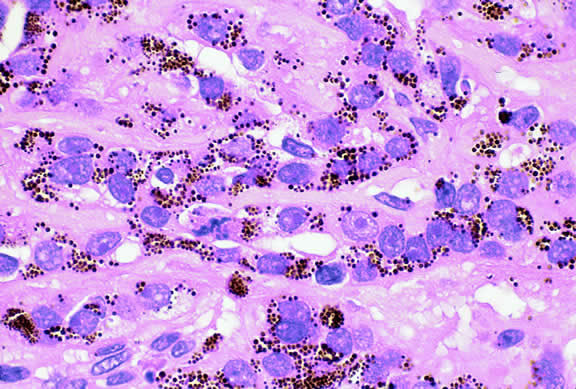

Epithelioid melanoma cells comprise the poorly differentiated end of the cytologic spectrum. Melanomas that contain epithelioid cells have a poorer prognosis. The term epithelioid meaning epithelial-like reflects the fanciful resemblance of the tumor cells to the cells of simple epithelia. Epithelioid cells have abundant cytoplasm and are often polygonal in shape (Fig. 33). They have distinct cytoplasmic margins, are poorly cohesive, and do not grow as a syncytium. The nuclei of epithelioid cells are usually round or oval and often appear vesicular because of margination or clumping of the chromatin along the inner side of the nuclear membrane. Epithelioid melanoma cells also have prominent nucleoli that are often large and reddish purple. Variants of epithelioid cells include relatively uniform small epithelioid cells (Fig. 34) and bizarre tumor giant cells that may appear wildly anaplastic (Fig. 35).

Fig. 33. Epithelioid melanoma cells. The cytoplasmic margins of these large, poorly cohesive epithelioid melanoma cells are easily discernible. Epithelioid cell nuclei are typically round and have peripheral margination of coarsely clumped chromatin. Epithelioid cells usually have prominent reddish purple nucleoli. They typically are polyhedral in shape and have copious amounts of cytoplasm. (Hematoxylin-eosin, × 250.)

Melanocytic tumors of the uvea are classified into four groups on the basis of cytology. Tumors composed entirely of spindle A cells or even blander nevus cells are classified as spindle cell nevi. Tumors composed of a mixture of malignant spindle A and spindle B cells are called spindle melanomas. Melanomas of mixed cell type contain a mixture of spindle and epithelioid melanoma cells (Fig. 42). Some laboratories specify the predominant cell type found in a mixed cell melanoma, for example, reporting mixed cell, predominantly spindle if only a few epithelioid cells are present. Epithelioid melanomas are composed predominantly of epithelioid cells. They are relatively rare and have the poorest prognosis. Most medium- and large-sized melanomas contain a mixture of spindle and epithelioid cells. In the COMS histopathology study, 86% of the posterior melanomas were classified as mixed cell type, 8% were of spindle cell type, and 5% were epithelioid.84 The association between cytology and mortality is known as the Callender classification.90 (See later section on prognostic factors.)

Fig. 42. Uveal melanoma, mixed cell type. Mixed cell melanomas are composed of a mixture and spindle and epithelioid cells. (Hematoxylin-eosin, × 250.)